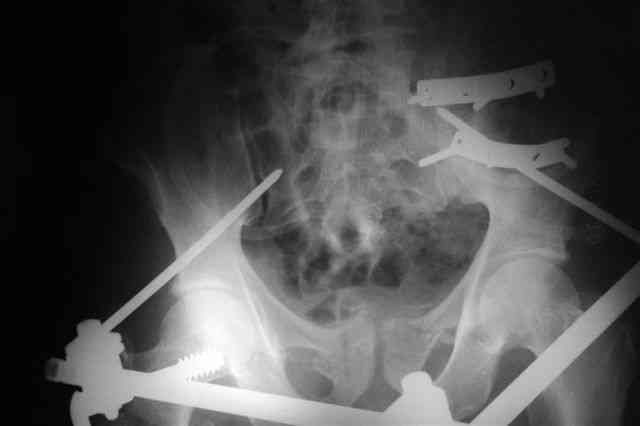

В приложении послеоперационные картинки.